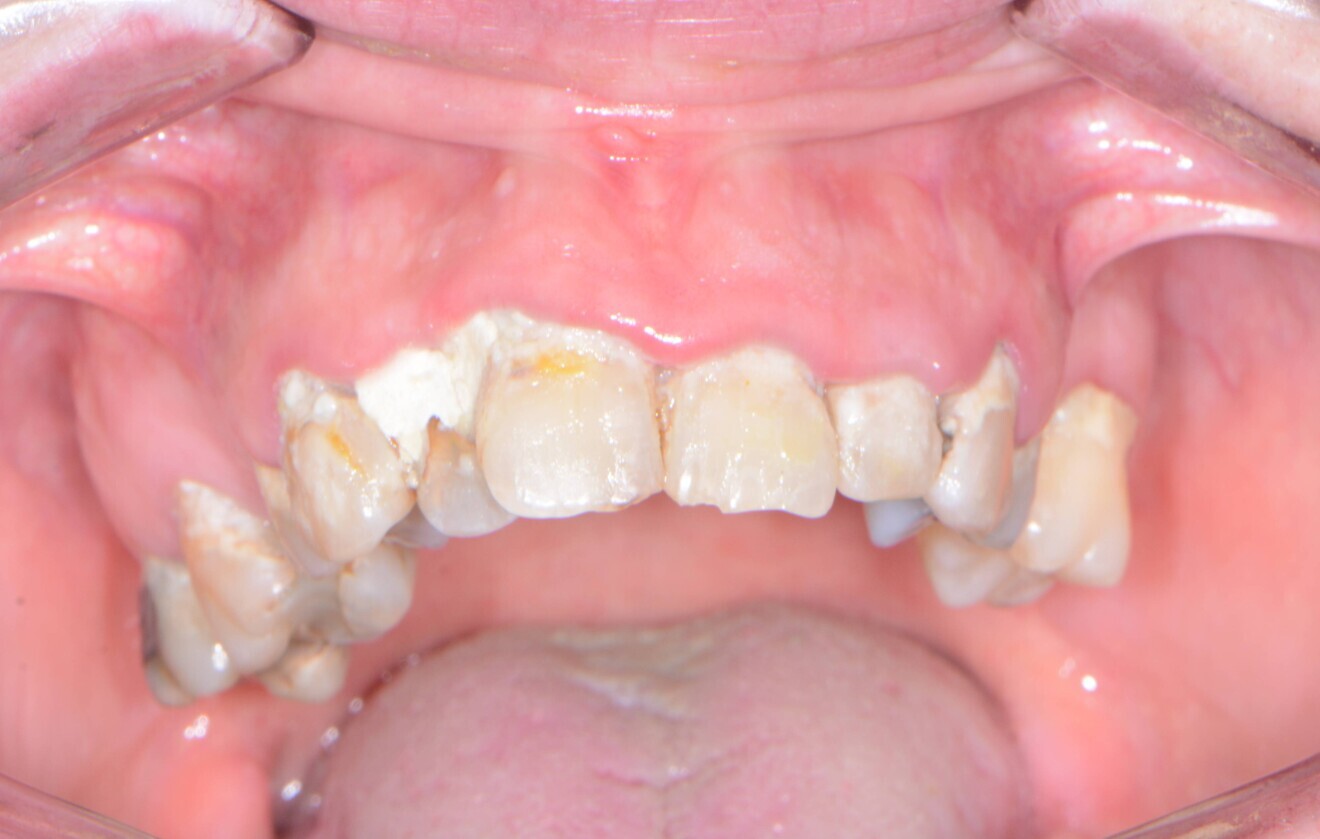

A patient presented to my practice for a consultation, wanting to restore her maxillary dentition to proper form and function (Figs. 1 & 2). She complained of generalised discomfort in these maxillary teeth apparently due to advanced decay as well as periodontal disease. Although her mandibular dentition would require definitive treatment in the future, the patient wanted to focus on her maxillary teeth at that time.

Fig. 1: Pre-op retracted frontal view.

Fig. 2: Pre-op occlusal view.